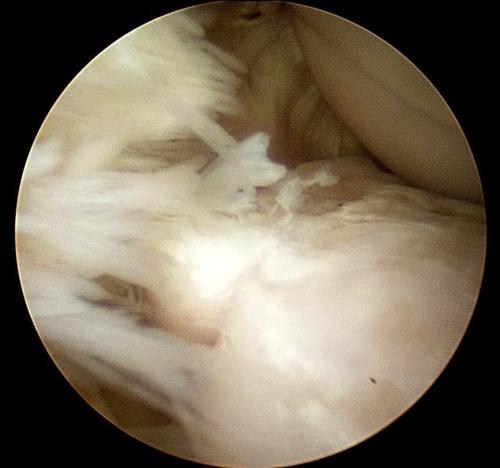

A rehabilitation program will be provided for your horse. This may also include suggestions for post-surgical treatments. For example, it is routine to perform Hyaluronic acid/corticosteroid injections at 2 weeks post surgery following arthroscopic chip/fragment removal. When there is substantial soft-tissue or cartilage injury, we often recommend biologic therapies.